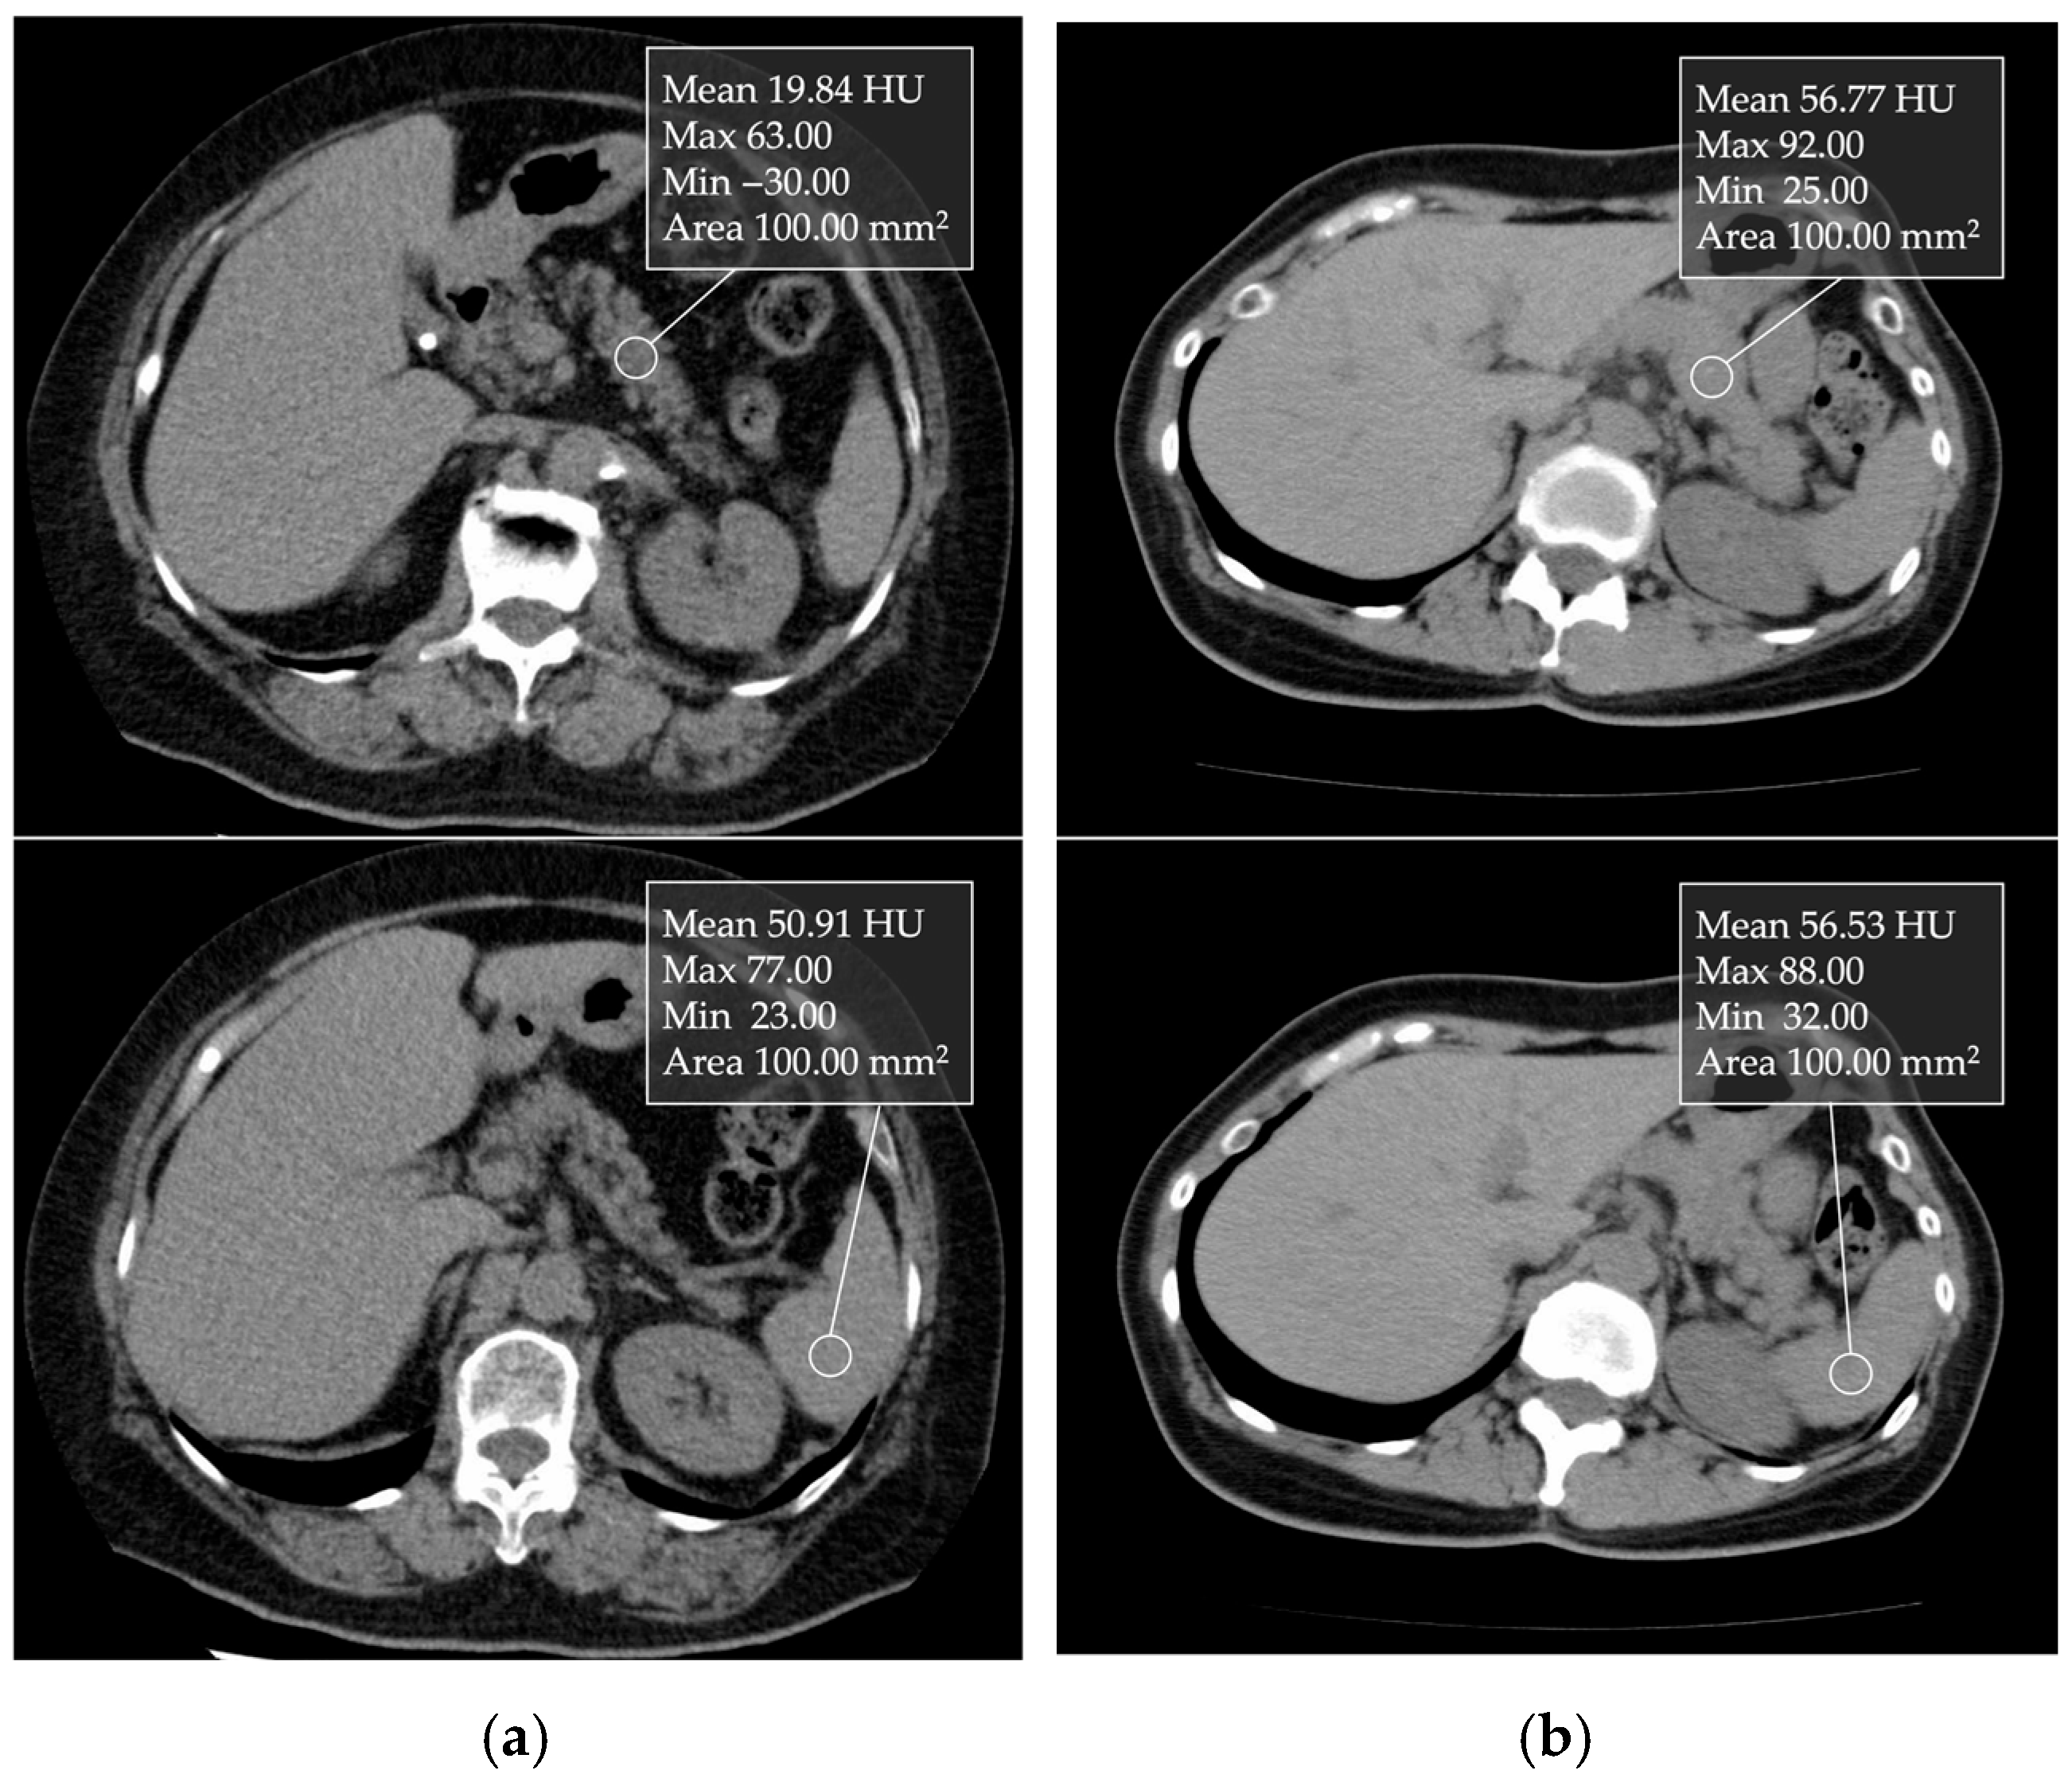

CT attenuation values can be measured in Hounsfield units (HU) (Figure 4). Kim et al. [38] reported that CT attenuation values can be used for a relatively good semiquantitative estimation of pancreatic fat content, as their findings demonstrated a correlation between CT parameters and histologically confirmed fat fraction. The decrease in pancreatic CT attenuation values on non-contrast enhanced CT images correlates with the degree of pancreatic fat infiltration [38,39]. The pancreas-to-spleen (P/S) CT attenuation value ratio is used to assess pancreatic fat. In addition, the absolute difference in CT attenuation values between the pancreas and spleen (P–S) has also been used. Additionally, Mori et al. [39] reported that when the P/S CT attenuation value ratio is less than 0.8, moderate or higher fatty deposits are observed in the pancreatic parenchyma in the histological evaluation of FP. This CT attenuation can be simply and easily measured in clinical practice.

Figure 4.

Unenhanced transverse CT images showing 1 cm ROIs placed in the nontumorous pancreatic parenchyma and spleen: (a) In a non-fatty pancreas, the pancreatic and splenic CT attenuation values were 56.77 and 56.53 HU, respectively. (b) In a fatty pancreas, the values were 19.84 and 50.91 HU, respectively.